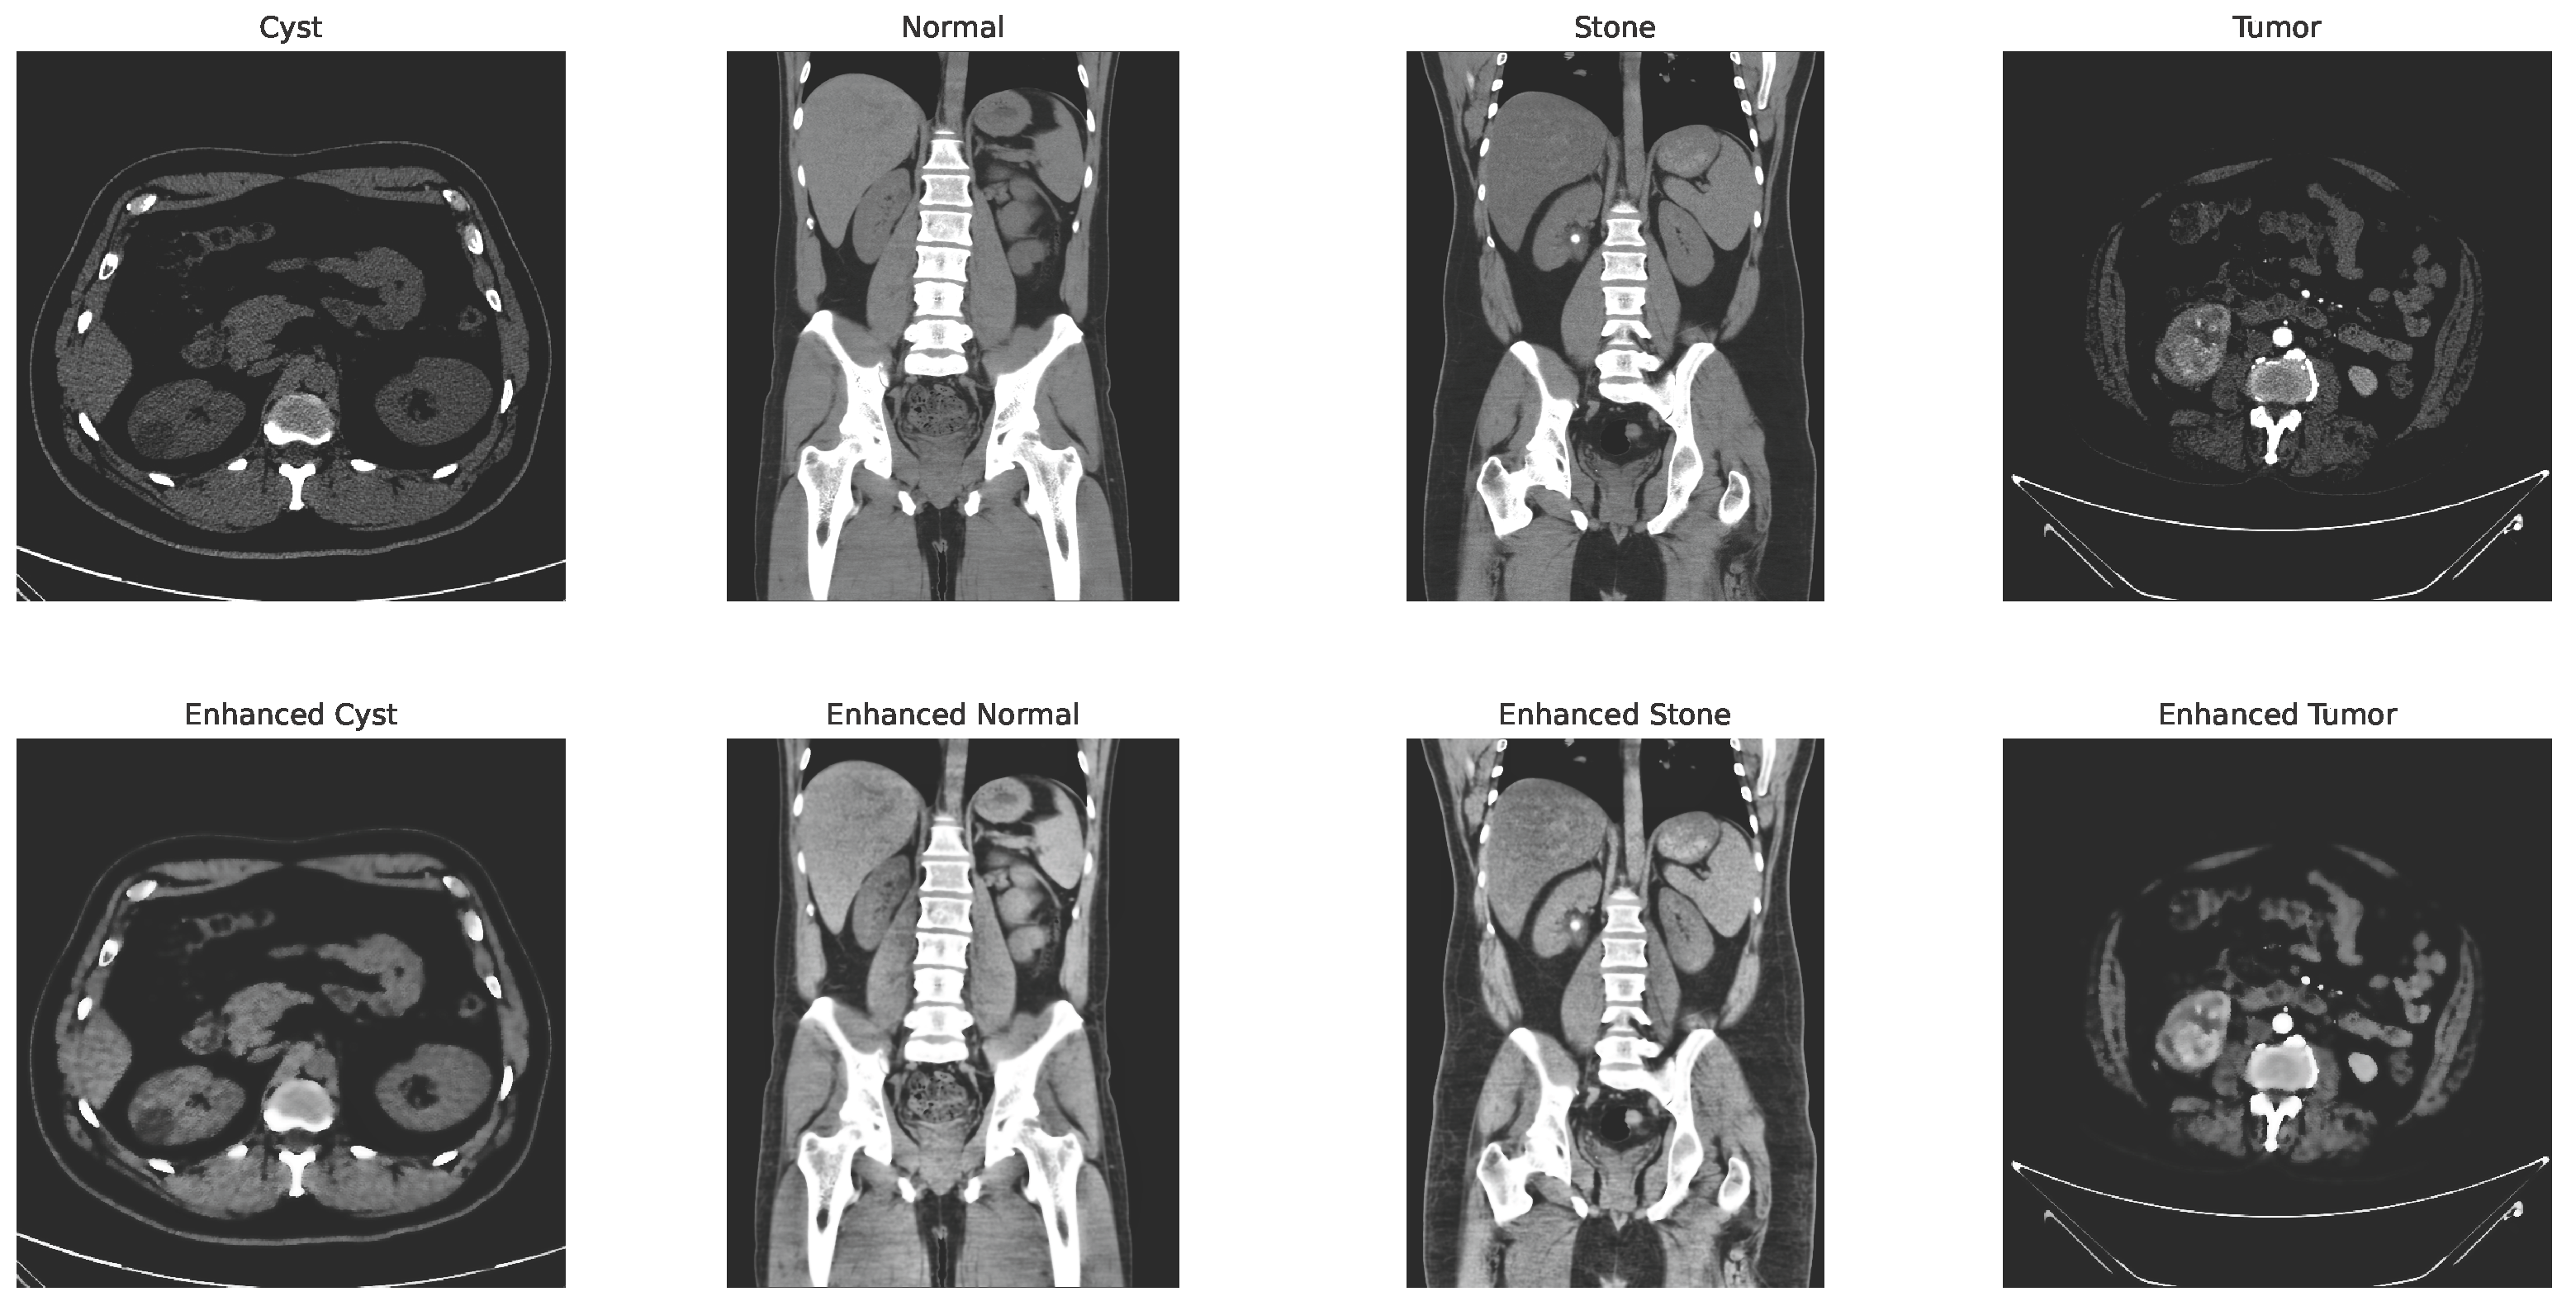

Some of the examples of the ct images of four classes are shown in Figure 3.

Figure 3.

Examples of cyst, normal, stone, and tumor CT image.